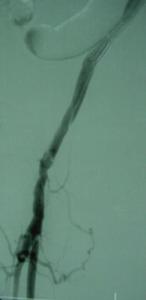

4.動脈造影 是確定診斷和制定手術方案的最重要手段,可精確了解動脈瘤及周圍血管的情況,特別是流入道和流出道的通暢情況,對動脈瘤切除、血管重建術式的選擇具有指導意義此外,也有助於發現其他部位的動脈瘤。

(2)術前進行精細的動脈造影以了解瘤體大小、流入道和流出道的通暢情況和其他部位有否動脈瘤